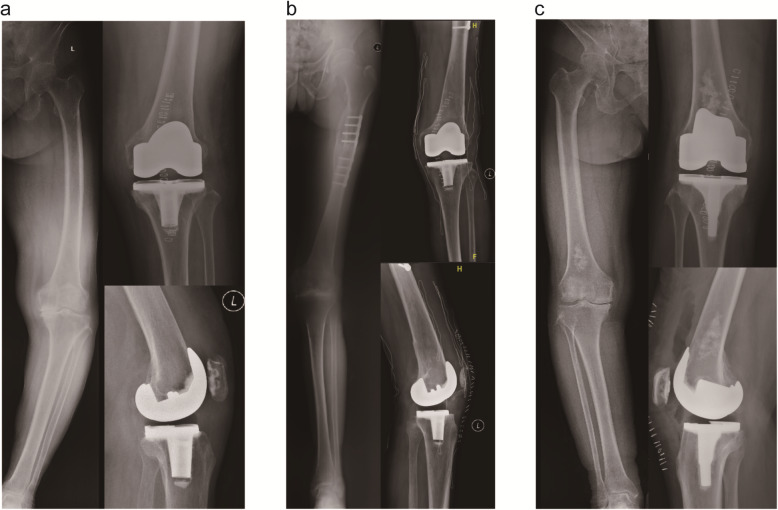

From the health economics standpoint, the value of new technology including computer navigation could be defined as the benefit divided by the cost [58]. Based on 2007 costings, Novak et al. employed a decision-analysis model to estimate the cost-effectiveness of CAS navigation in TKA, determining that cost-savings could be achieved in the long-term if the cost of CAS navigation was $629 or less per operation [59]. Thus selective use of the ABN would be an optimal strategy, we proposed several suitable indications of the ABN based on our clinical experiences and previous research. For patients with a femoral or tibial EAD, being accurate could be technically demanding [33], in which cases surgeons might fail to figure out the proper valgus cut angle of distal femur (Fig. 2a). In such cases, the ABN system appeared to be valuable [60]. Individuals with lower limb fracture malunion may develop EAD and/or have hardware (Fig. 2b). It was also a potential advantage of the ABN to obtain the desired component positions without irritating the medullary. In the similar rationale, the surgery was performed for one patient with benign bone tumor in distal femur uneventfully with the use of iAssist, without offending the tumor (Fig. 2c). Moreover, for individuals with extraordinary anterior femoral bowing, similar to those with an EAD, femoral component flexion would have a significant increase [61]. Utilising ABN could also make sense.

Fig. 2.

a Pre- and postoperative radiographs of patient with femoral EAD. b Pre- and postoperative radiographs of patient with lower limb fracture malunion and hardware retaining. c Pre- and postoperative radiographs of patient with benign bone tumor in distal femur